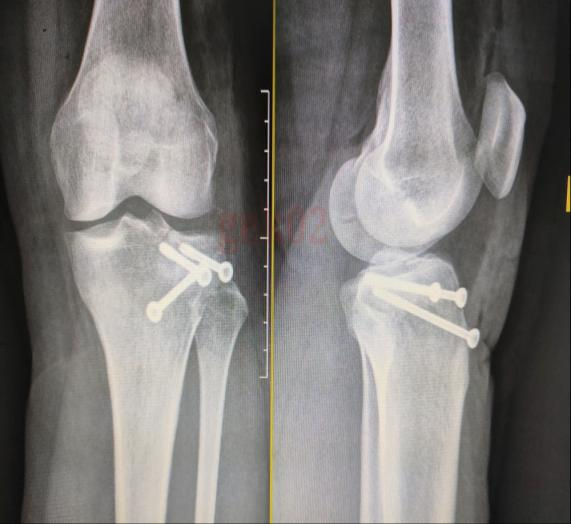

DR检查(数字化X射线摄影)

DR是传统X光片的升级版,其采用数字化技术,成像更清晰,检查更便捷。

1.成像速度快:检查过程只需几分钟,适合急诊或大规模筛查。

3.二维平面图像:提供的是平面影像,适合观察骨骼、肺部等结构。

●骨折诊断:如四肢、脊柱、胸骨等部位的骨折。

●初步筛查:DR是许多疾病的第一道筛查工具,尤其是肺部疾病和骨骼病变。

●快速诊断:在急诊中,DR可以帮助医生快速判断是否存在骨折、气胸等问题。